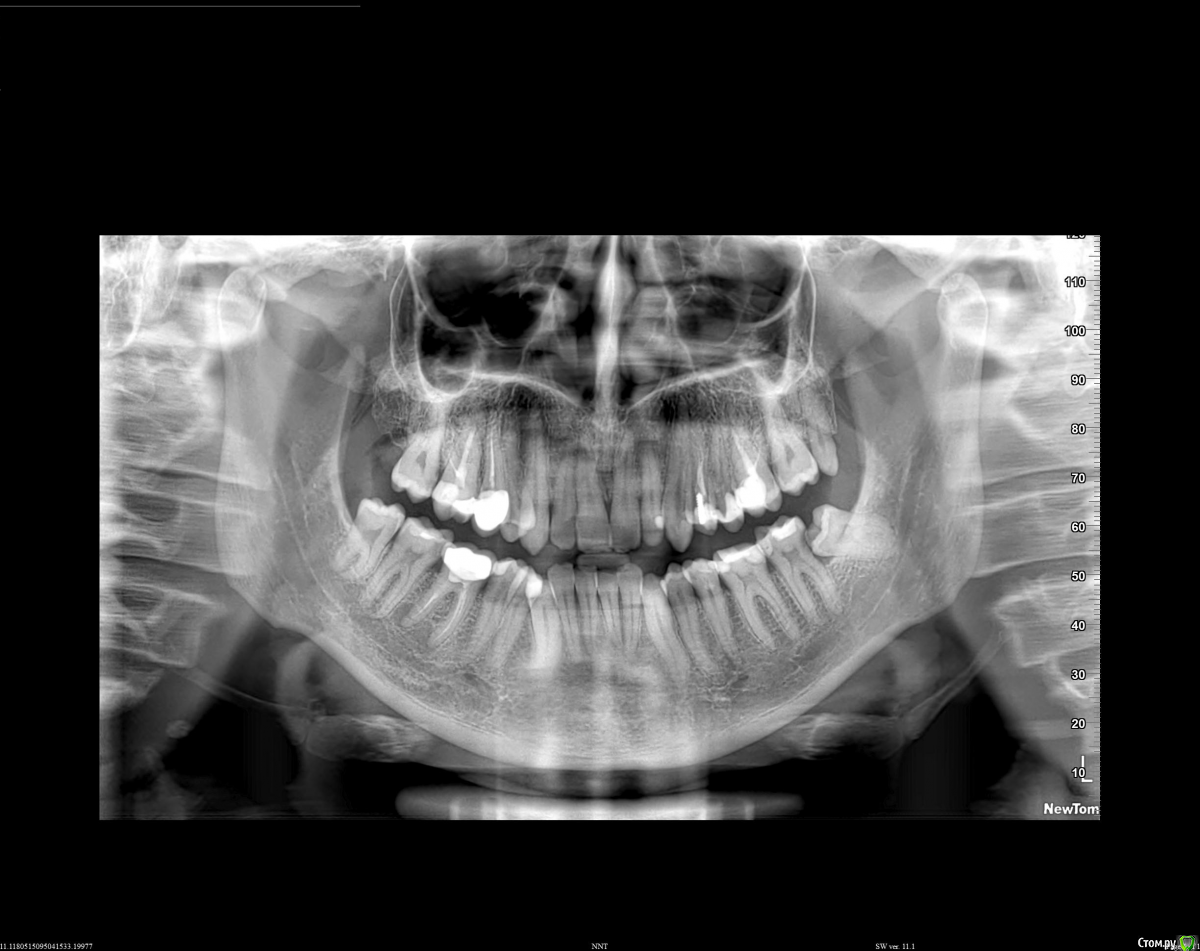

Alexm Опубликовано 15 июля, 2020 Поделиться Опубликовано 15 июля, 2020 (изменено) Всем доброго дня! Посмотрите пожалуйста на снимок, в особенности на корни зубов с коронками, есть ли какие то диагнозы или комментарии. Спасибо за помощь! Изменено 15 июля, 2020 пользователем Alexm Ссылка на комментарий

St. Опубликовано 16 июля, 2020 Поделиться Опубликовано 16 июля, 2020 Добрый день. Что Вас беспокоит?Есть несколько вопросов: воспаление за пределами корня 6 зуба внизу справа(тот что под коронкой), удаление зуба мудрости внизу слева и лечение соседнего, плановое перелечивание каналов ранее леченых зубов на верхней челюсти и их протезирование Ссылка на комментарий